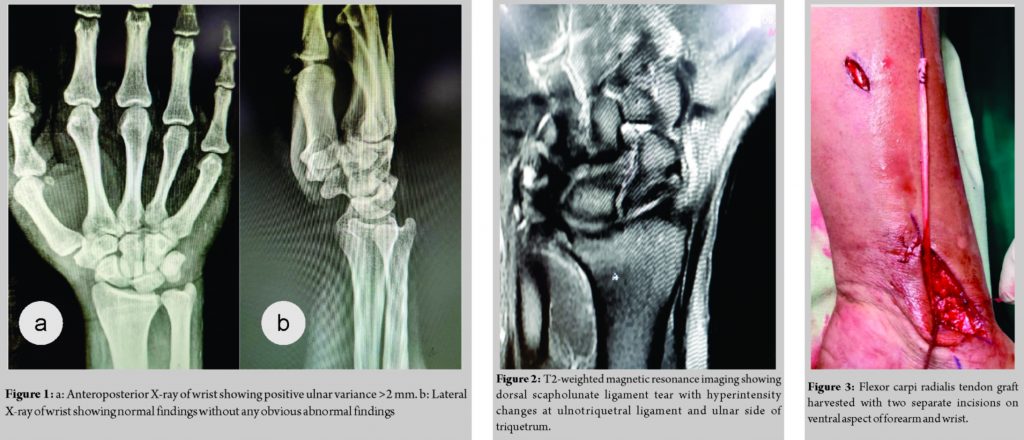

A 30-year-old male complains of the right wrist pain for 6 months due to fall on an outstretched hand. The patient was treated with below elbow cast for 6 weeks. Since then, the patient had wrist pain around ulnar the head by clicking on pronation, palmar flexion, and ulnar deviation. Range of motion was painful after 70° of palmar flexion, 10° of ulnar deviation with pronation. The scaphoid shift test and fovea sign test were negative whereas ulnocarpal stress test was positive. Anteroposterior view of wrist X-ray showed positive ulnar variance >2 mm, whereas the lateral view showed normal findings (Fig. 1). Magnetic resonance imaging (MRI) revealed dorsal scapholunate ligament tear with hyperintensity changes of ulnotriquetral ligament and ulnar side of the triquetrum (Fig. 2). Pre-operative disabilities of the arm, shoulder, and hand (DASH) score was 40.4 and visual analog score (VAS) score was 7. The patient was planned for modified Brunelli technique proposed by Elsaftawy et al. in which reconstruction of the scapholunate ligament with transfer of partial flexor carpi radialis tendon (Fig. 3) from plantar to the dorsal side through the distal pole of scaphoid and is anchored to the lunate with a specialized suture anchor, and extra-articular ulnar shortening osteotomy for positive ulnar variance in one setting. The patient was kept in below elbow dorsal slab for 6 weeks. After 6 weeks, wrist range of motion was gradually started. Heavy work started after 3 months. The patient had full range of motion at 6 months with DASH score of 10 and VAS score of 1 with complete radiological union at 1-year follow-up (Fig. 4).